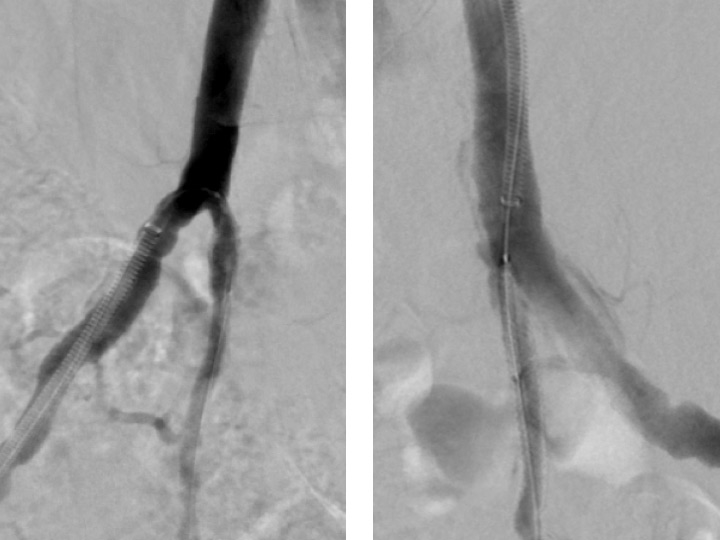

Figure 3

Sub-total occlusion of both hypogastric arteries (*) in a patient with cardiovascular risk factors and erectile dysfunction.

Figure 4

Angiographic result after bilateral placement of drug eluting stents.

Endovascular therapy for obstructions of the common iliac and hypogastric arteries has traditionally been performed for many years. Figures 3 and 4 show angiograms of the pelvic arteries of a 62-year-old architect with erectile dysfunction. He had undergone aorto-coronary bypass grafting 3 years previously and, based on duplex ultrasound, an arterial inflow obstruction had been diagnosed. On intra-arterial angiography, a high-grade obstruction of both hypogastric arteries was diagnosed (fig. 3), both of which have been stented using drug-eluting stents (fig. 4). Erectile dysfunction in this patient was significantly improved during follow-up.